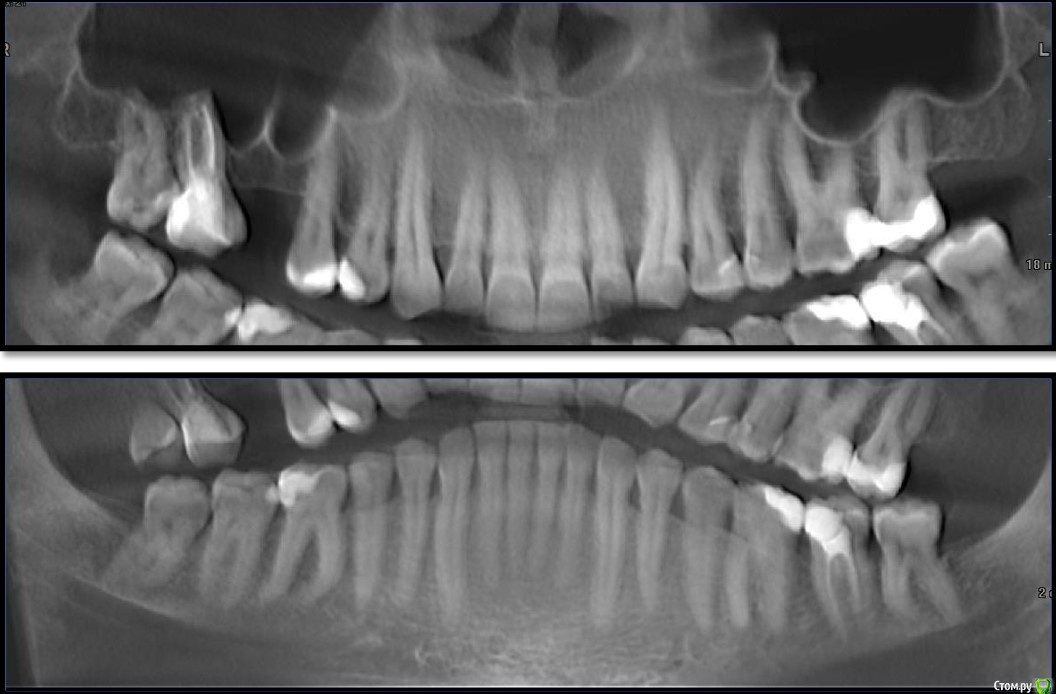

al7777 Опубликовано 10 января, 2021 Поделиться Опубликовано 10 января, 2021 Добрый день.У меня подходит к завершению лечение брекетами и нужно делать имплантацию верхней шестерки справа.Когда касался этого вопроса лет 5 назад, говорили, что нужен открытый синус-лифтинг. Проблема в септе, которая делит место для зуба надвое. Высота кости в этом месте около 4 мм, на снимке видно измерение.Сейчас 2 разных врача предложили сделать закрытый синус-лифтинг.Хотелось узнать мнение уважаемых специалистов с форума по этому поводу. Первый вариант - Установка короткого импланта большого диаметра (5х8 вроде) прямо под септой, синус-лифтинг будет "без применения костнозамещающего материала", имплант Корейский Implantium. Второй вариант от другого доктора- Установка импланта несколько под углом, так чтобы увеличить длину его контакта с костью и выйти с одной стороны от септы. От септы мембрану в пазухе не отслаивать, так как она при этом порвется, а синус-лифтинг сделать закрытым способом, с одной стороны от септы, там где выйдет имплант. Имплант корейский Осстем (можно и Штрауман поставить, но по деньгам сейчас не потяну), плюс пластика мягких тканей. Снимки прикладываю, единственное панорамные снимки сделаны перед установкой брекетов, не смог сейчас сделать панораму с КТ Пикассо. Ссылка на комментарий